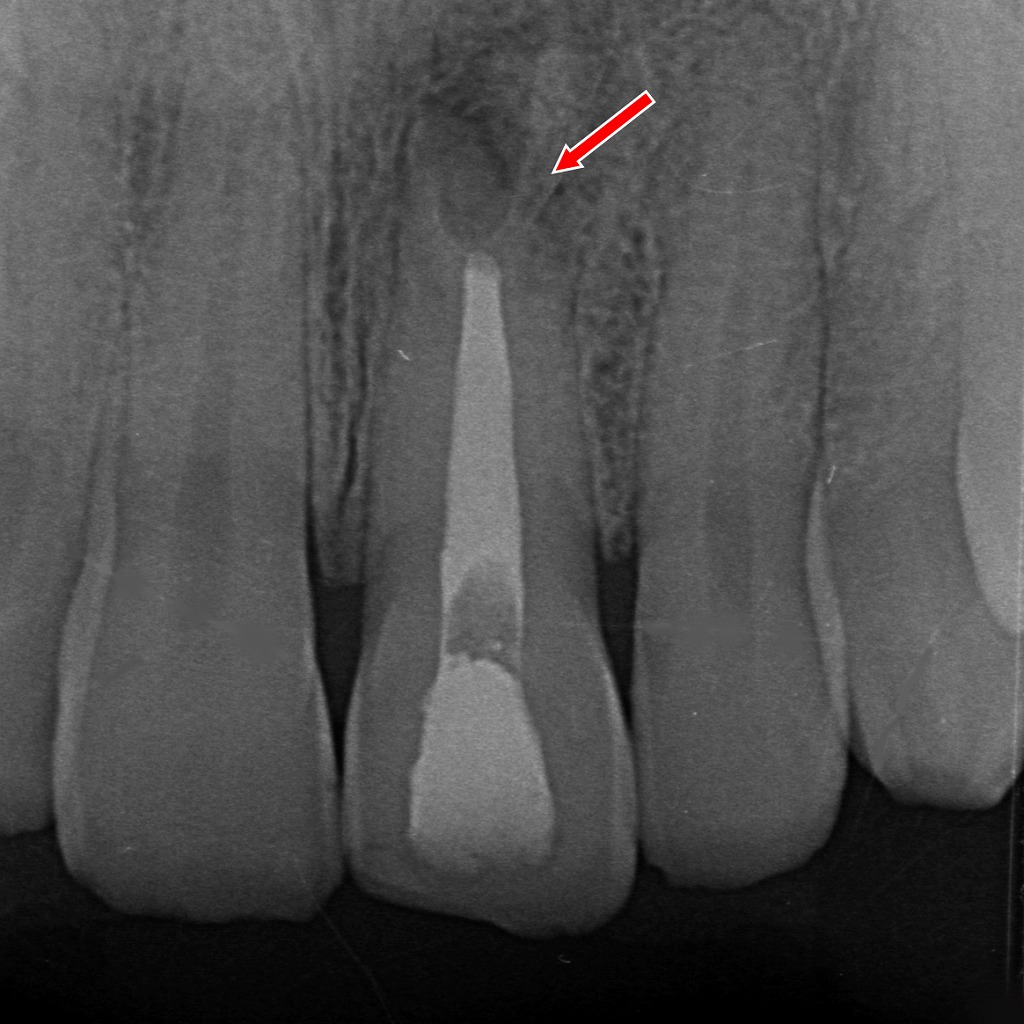

📌 画像の解説:病的歯根吸収の根充後・経過観察

矢印で示された部位には、外部吸収(external resorption)によって生じた不規則な透過像が依然として認められます。これは、歯根外側の歯質が溶けた部分を示す典型的な像です。

一方、根管内部には根充材が均一に充填されており、根管の封鎖は良好です。再感染リスクを最小限に抑えた状態が維持されていると判断できます。

✔ 経過観察時のポイント

- 吸収部の透過像はすぐには消失しない

外部吸収は骨や歯根膜の再生とともに徐々に変化するため、複数ヶ月~年単位の観察が必要です。 - 根充材の位置は安定しており、内部からの感染源は遮断されている

治療としては適切に封鎖されている状態。 - 新たな拡大や境界不明瞭化がないかが観察上の重要点

今回の画像では、

👉 吸収部は残存しているものの、病変の拡大を示唆する所見は乏しく、根管治療後としては良好な経過が期待できる状態

と評価できます。